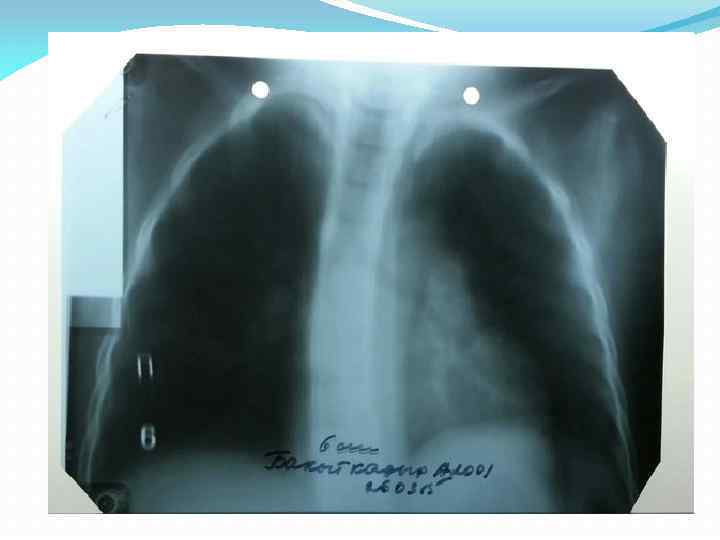

R-графия грудной клетки от 26. 03. 15 г. Заключение: легочные поля с обоих сторон прозрачные. Корни легких справа - структурные, слева - в области тела в головке корня отмечается дополнительное образование, обусловленные увеличенными лимфоузлами. R-графия грудной клетки от 31. 03. 15 г. Заключение: легочные поля прозрачные. Легочный рисунок усилен в прикорневой зоне, больше слева. Корни легких структурные , слева – головка корня инфильтрированное. Верхнедолевой бронх слева завуалирован. Синусы свободные. Тень средостения не изменена. Справа – границы в пределах возрастой нормы.